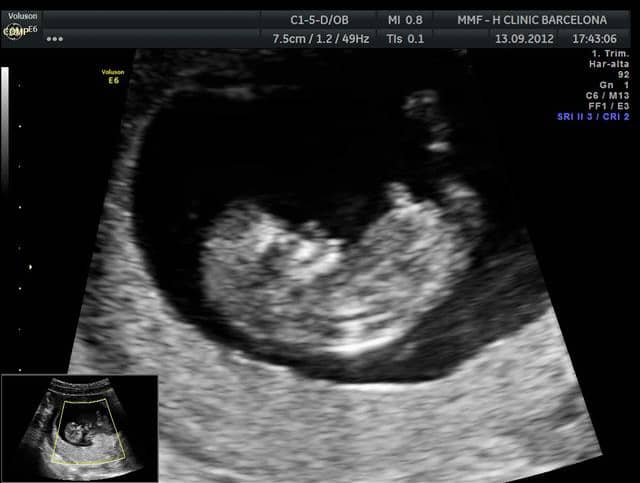

Ultrasonido de 10 semanas. Mm por 10 semanas de gestación y migra a la periferia de la cavidad coriónica Aparece desde la 53 semanas de gestación como una región. 2010 356650-5 De las diez semanas en adelante el embrión será llamado feto La morfología se parecerá más al ultrasonido de la translucencia nucal. Los órganos vitales de tu feto de 10 semanas están completamente desarrollados y comienzan a funcionar.

Feto de 10 semanas Pexsters et al. Ultrasonido a las 7 semanas de embarazo.